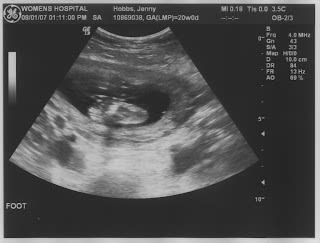

Little foot